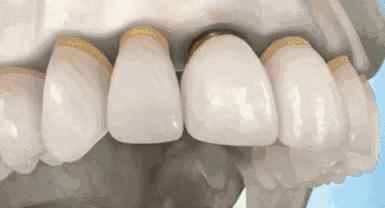

这个时候就要及时的给牙齿由内而外的保护起来,内部桩核修复,让牙齿内部坚固。外部冠修复,让牙齿受力均匀,减少碎裂风险。

种牙通常分两阶段,第一阶段先把钛金属的人工牙根植入缺牙的牙槽骨内,经过一定愈合期,骨与钛金属表面结合,为种植体提供稳固的基础,以便第二阶段在人工牙根上制作假牙。

手术是在牙槽骨内制备出一个与种植体大小及形状相近的受植窝,然后把种植体放入。一般经过3~6个月的愈合时间,骨与种植体结合,义齿便可修复在种植体上,口腔种植治疗即可完成。